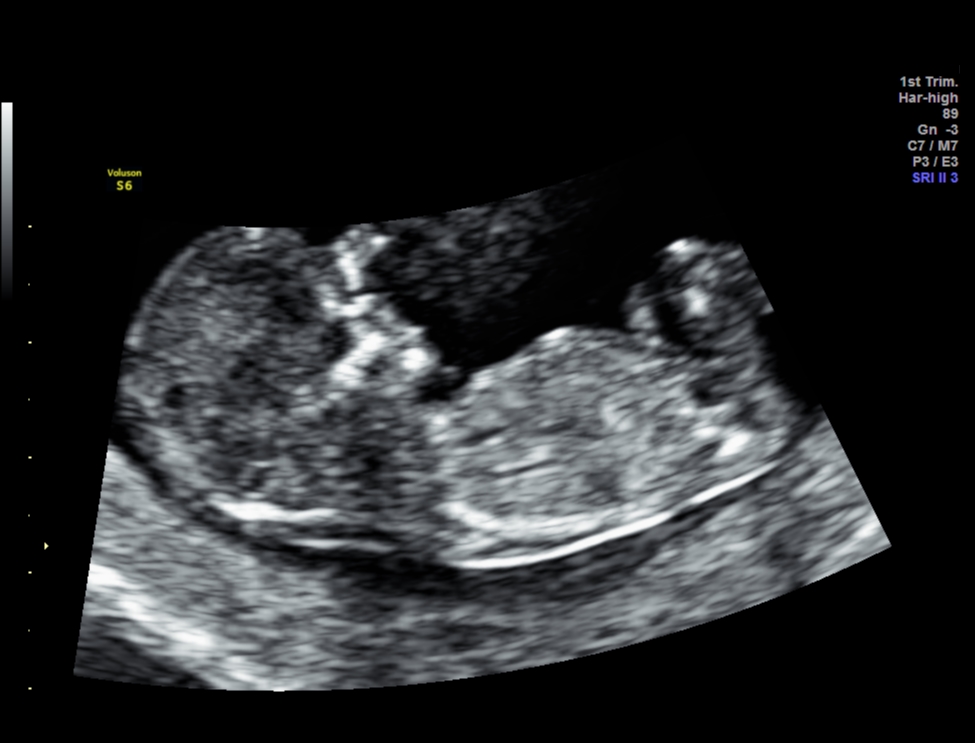

Attachment 33526Attachment 33527

HI everyone, This is my 1st post in this forum after reading many threads about gender predictions and some of you ladies are very knowledgable. These are my NT scan pics for today.

One picture I asked tech what the gender is and she said she was very unsure but it might develop to girl part. What do you guys think? I googled some boys potty shot also has three lines and why mine is protruding ???